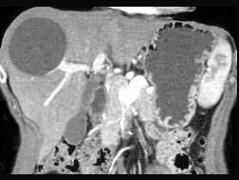

女性,45岁,偶有右上腹部胀痛,CT检查见图,最可能的诊断是 ( )A、肝血管瘤B、肝棘球蚴病C、肝囊肿D、肝脓肿E、肝癌

问题 女性,45岁,偶有右上腹部胀痛,CT检查见图,最可能的诊断是 ( )

选项 A、肝血管瘤 B、肝棘球蚴病 C、肝囊肿 D、肝脓肿 E、肝癌

答案 C